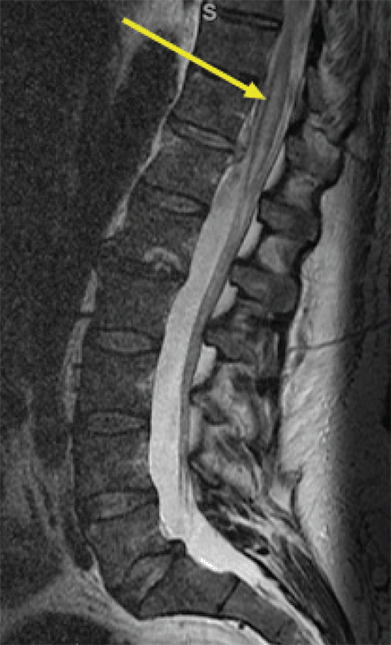

On post-procedure day one, the patient continued to demonstrate three out of five strengths in bilateral lower extremities, with preserved sensation. On post-procedure day two, the patient was extubated, and the vasopressors were weaned off. An MRI of the lumbar spine demonstrated an anterior spinal cord infarct spanning T9 to L1, as well as an epidural hematoma at the T11/T12 levels and demonstration of the T12 vertebral body fracture (Figure 3). Spine surgery was consulted, who recommended continued conservative management. On post-procedure day five, the patient was transferred from the intensive care unit to a spine floor. He demonstrated neurogenic bowel and bladder dysfunction, requiring intermittent urinary catheterizations and daily suppositories and rectal stimulation.

Figure 3. Acute Spinal Cord Infarction of T9-L1, T12 Vertebral Body Fracture and Associated Hematoma. Published with Permission